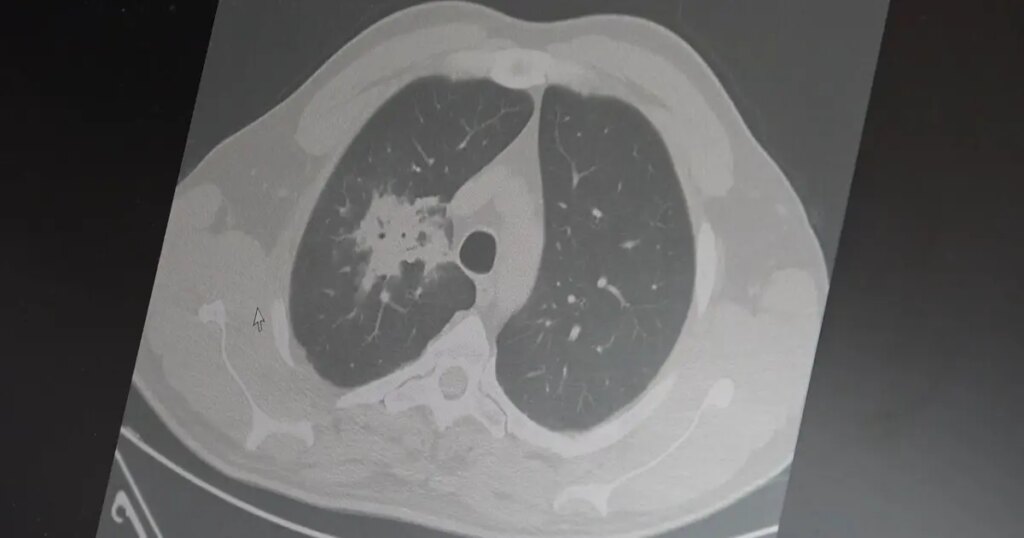

Özkaya, 100’den fazla bilimsel çalışmayı incelediklerini ve elektronik sigaraların özellikle akciğer ve ağız kanserini teşvik edebileceğini gösteren ciddi bulgular edindiklerini belirtti. Uzun vadeli sonuçların henüz tam olarak belirlenmediğini, ancak elde edilen erken verilerin düşündürücü olduğunu vurguladı.

Araştırmalarda insan, hayvan ve laboratuvar verilerinin birlikte ele alındığını aktaran Özkaya, elektronik sigaraların içerdiği kimyasalların hücre düzeyinde sürükleyici zararlara yol açtığını ifade etti.

Elektronik sigaraların DNA hasarı, oksidatif stres ve kronik iltihaplanmayı tetiklediğini belirten Özkaya, “Bu üç faktörün doğrudan kanser oluşumuna yol açtığını biliyoruz,” dedi.

2024 yılında yayımlanan bir çalışmaya dikkat çeken Özkaya, hem geleneksel hem de elektronik sigara kullanan bireylerin akciğer kanseri riskinin, yalnızca geleneksel sigara içenlere göre dört kat daha fazla olduğunu kaydetti.